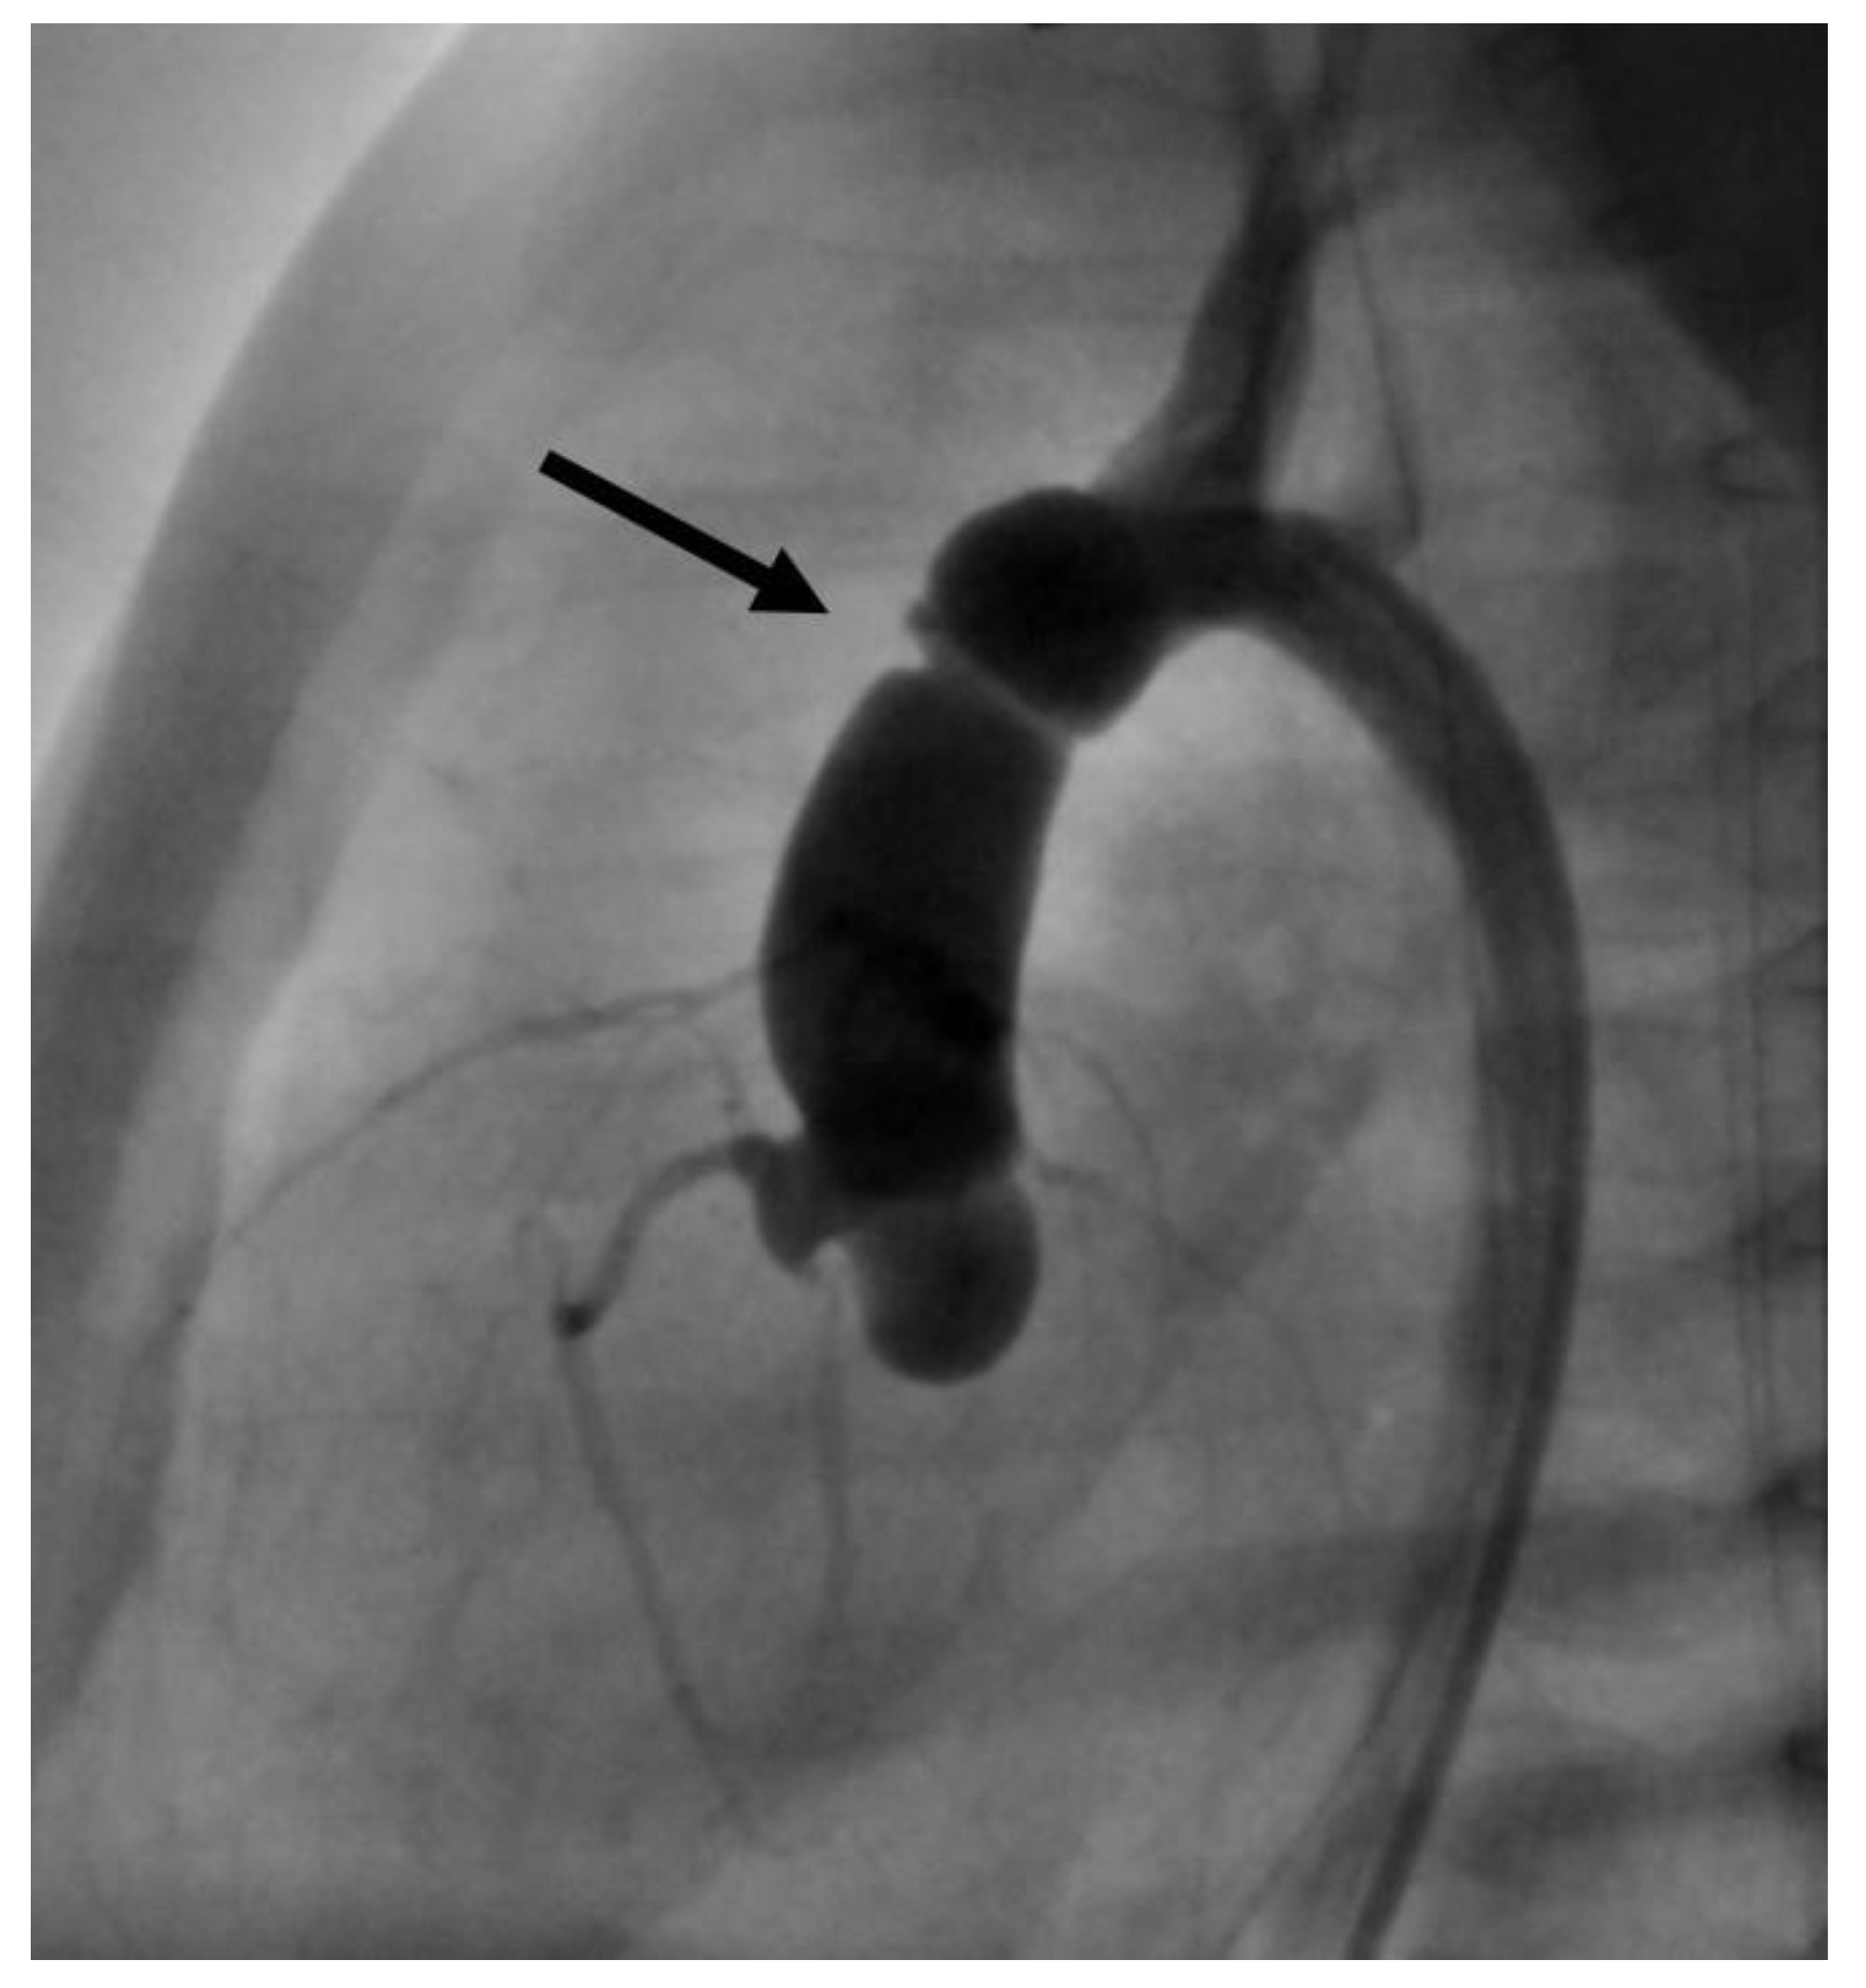

- In case 2, there was an air embolism in the left ventricle during the patient’s first catheterization. Due to depressed LV function with low contractility, the air bubble remained ventrally in the LV (Figure 8), where we managed to extract it with the catheter.